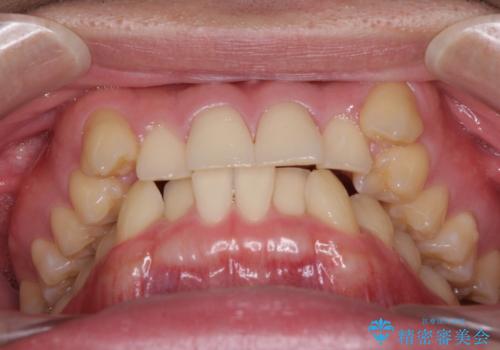

- 上顎の八重歯と前歯のデコボコを気にして来院された患者様です。

八重歯の移動量が多く、インビザライン単体での治療は困難と判断し、補助装置により八重歯移動後にインビザラインを用いることとしました。

上顎のみの抜歯矯正をインビザラインで行う場合、奥歯の前方移動がインビザラインでは苦手のため、奥歯の咬み合わせが不十分となることがあります。

今回の治療では終了時に奥歯は接触しているものの、接触の程度は物足りないものがある状態でした。今後保定期間に少しずつ奥歯の咬合を改善させていくことになります。